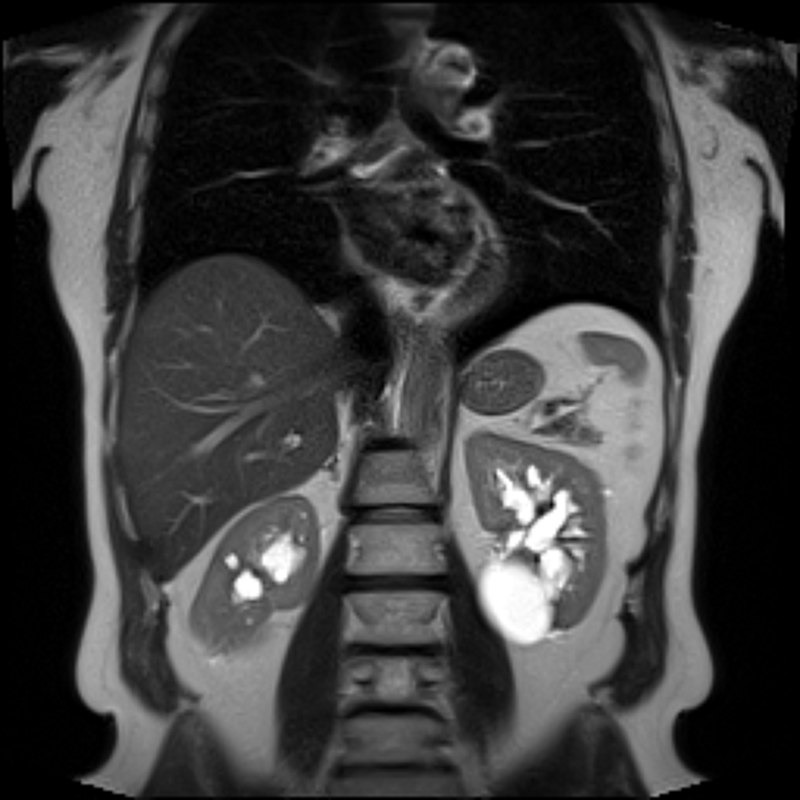

أكياس الكلى:

عبارة عن جيوب دائرية الشكل وغير سرطانية، مملوءة بسائل مائي يتكون داخل الكليتين أو على سطحهما الخارجي، ونادرا ما تؤثر على وظائف الكلى وتكون عادة التكيسات الكلوية البسيطة.

⬅️التصوير بالرنين المغناطيسي (MRI)